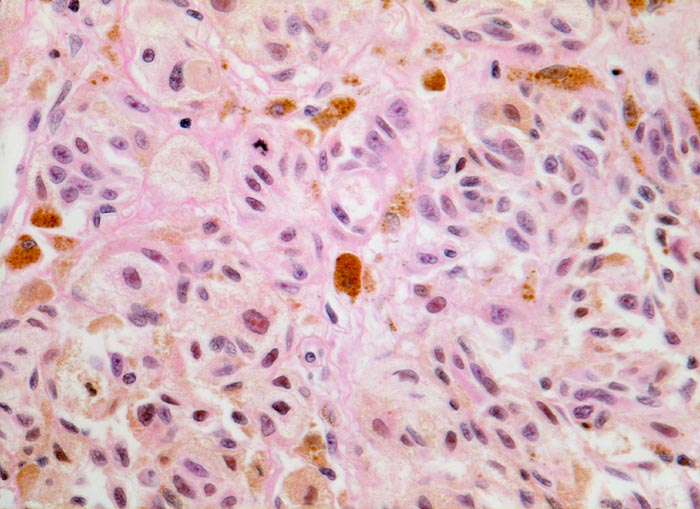

Malignes Melanom

Atypische pigmentierte Zellen mit reichlich Zytoplasma und vergrösserten atypischen Kernen mit prominenten eosinophilen Nukleolen. Mitose. Zwischen den Tumorzellen Melanophagen mit grobgranulärem intrazytoplasmatischem Pigment.

Der Nachweis von Mitosen in intradermal gelegenen Melanozyten spricht für das Vorliegen eines malignen Melanoms.